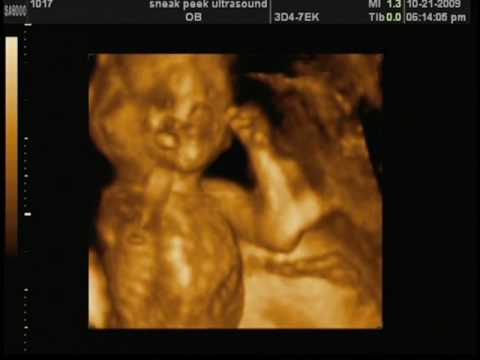

Sneak Peek Ultrasound, Lafayete LA, TV Commercial - YouTube

3D/4D ultrasound - 34 Weeks - YouTube

What Is 4D ultrasound Scan? - YouTube